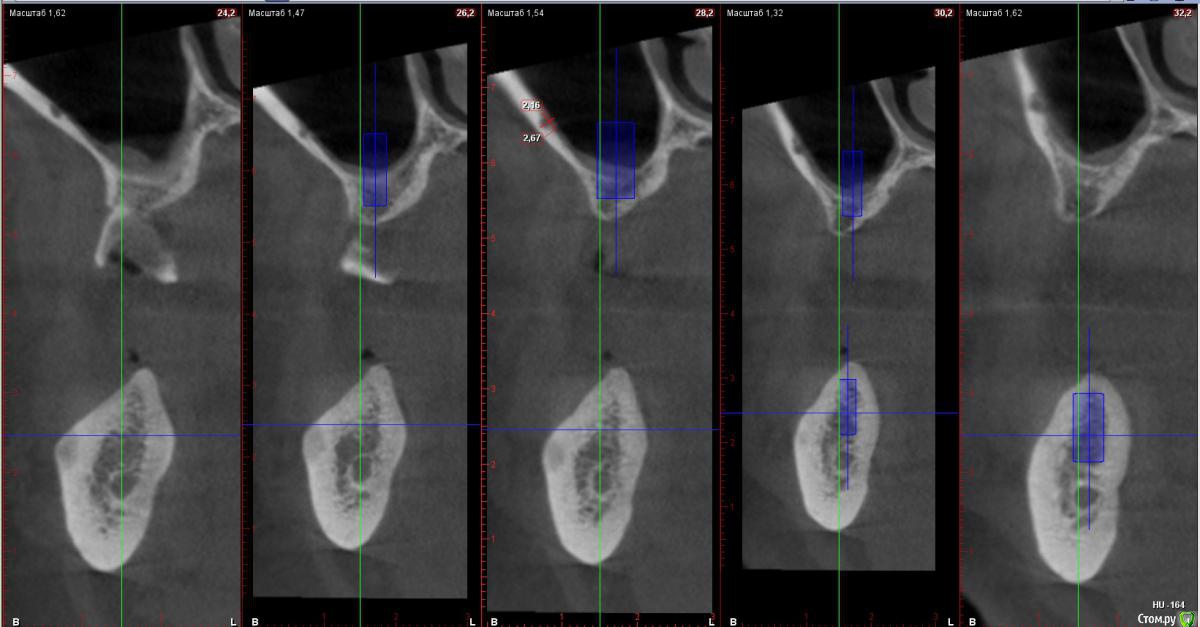

kamranchick Опубликовано 29 ноября, 2017 Поделиться Опубликовано 29 ноября, 2017 Господа, есть мысли? как формировать окошеечкоЛибо игнорировать данный сосуд*?) Ссылка на комментарий

Irouil Опубликовано 29 ноября, 2017 Поделиться Опубликовано 29 ноября, 2017 Может вертикально? Как Олег Юрьевич учил. Ссылка на комментарий

АнтонТЛТ Опубликовано 29 ноября, 2017 Поделиться Опубликовано 29 ноября, 2017 Я бы игнорировал)) риммер поменьше и вперед)) Ссылка на комментарий

АнтонТЛТ Опубликовано 30 ноября, 2017 Поделиться Опубликовано 30 ноября, 2017 Риммер под сосуд) 1 Ссылка на комментарий

red_butler Опубликовано 30 ноября, 2017 Поделиться Опубликовано 30 ноября, 2017 делать открытый, сосуд можно заколотить 1 Ссылка на комментарий